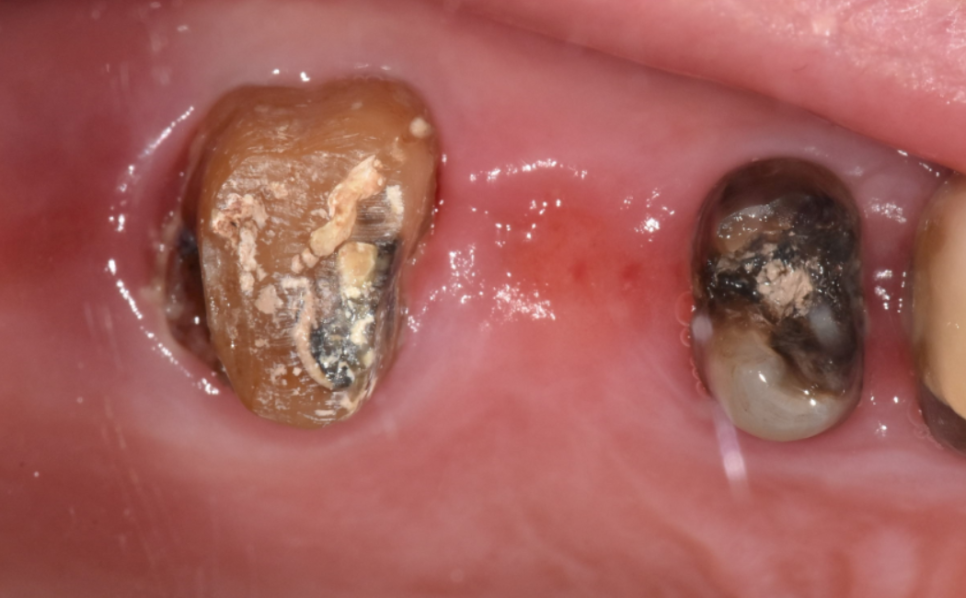

한눈에 보기에도 상태가 좋지 않죠~?

치아 내부에 충치가 심하고

푸석거려서

살리기 어렵다 말씀드렸습니다.